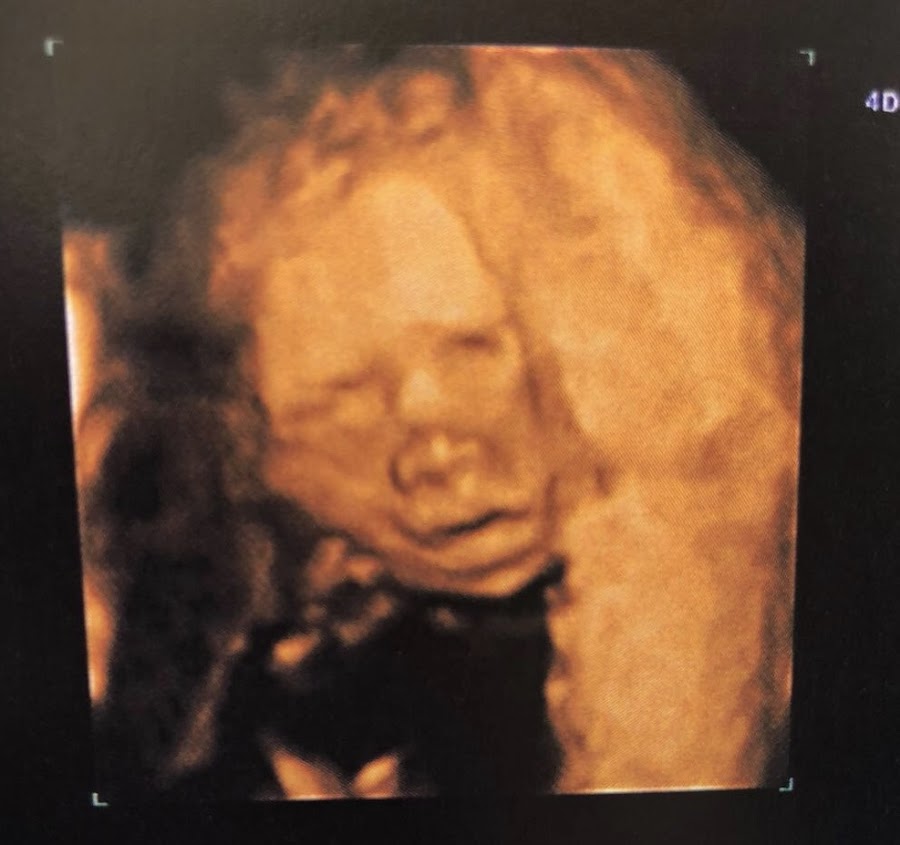

- Eco de las 20 semanas. Le vimos ayer, y su tamaño justifica mi tripota, está grande, o "espigado" como dijo la doctora. Tenía todas sus cositas en su sitio y todo funcionaba bien. A pesar de lo tranquila que iba no pude evitar emocionarme, es que su corazón es música para mis oídos...